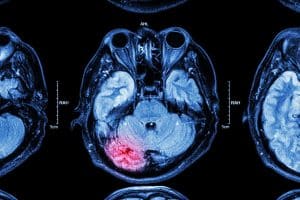

Types of brain injuries caused by car accidents

Car accidents can cause the following brain injuries:

- Penetration injuries. An external object can penetrate through your skull and cause serious damage to your brain.

- Diffuse axonal. You can suffer from a diffuse axonal head injury when the parts of the brain structure tear. When your body comes to a sudden stop, your brain can crash against your skull. This type of brain injury often happens in high-speed car accidents.

- Coup-contrecoup. A coup-contrecoup head injury happens when the brain suddenly jerks against the skull. The impact from the car accident causes the brain to hit against both sides of the skull. As a result, both sides of the brain end up damaged.

- A concussion occurs when the brain hits the inside of the skull from a sudden change of movement. The severity of a concussion can vary and can cause serious symptoms like dizziness, fatigue, or personality changes.

- A contusion is a head injury where the brain suffers bruising. This type of brain injury usually results from direct impact to the head. When your head is struck by other external objects or your head hits a fixed object in the car, you can experience a contusion.